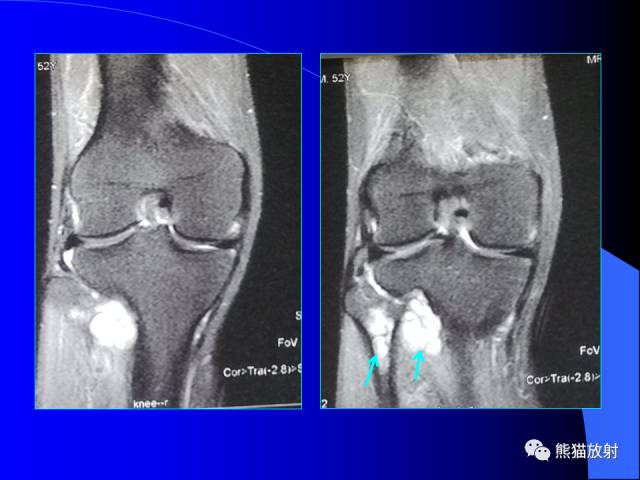

膝关节周围囊肿是较常见的病变,可以是原发的,多见于青年及儿童,囊内容物通常是黏液;也可以是继发的,多与关节腔相通,内含一般黏性的滑液,常继发于膝关节骨关节炎、类风湿关节炎、非特异性滑膜炎、半月板损伤、髌骨软骨软化症等。

以上滑囊出现炎症时均可形成滑囊囊肿。

腘窝囊肿是膝关节周围最常见的囊肿。